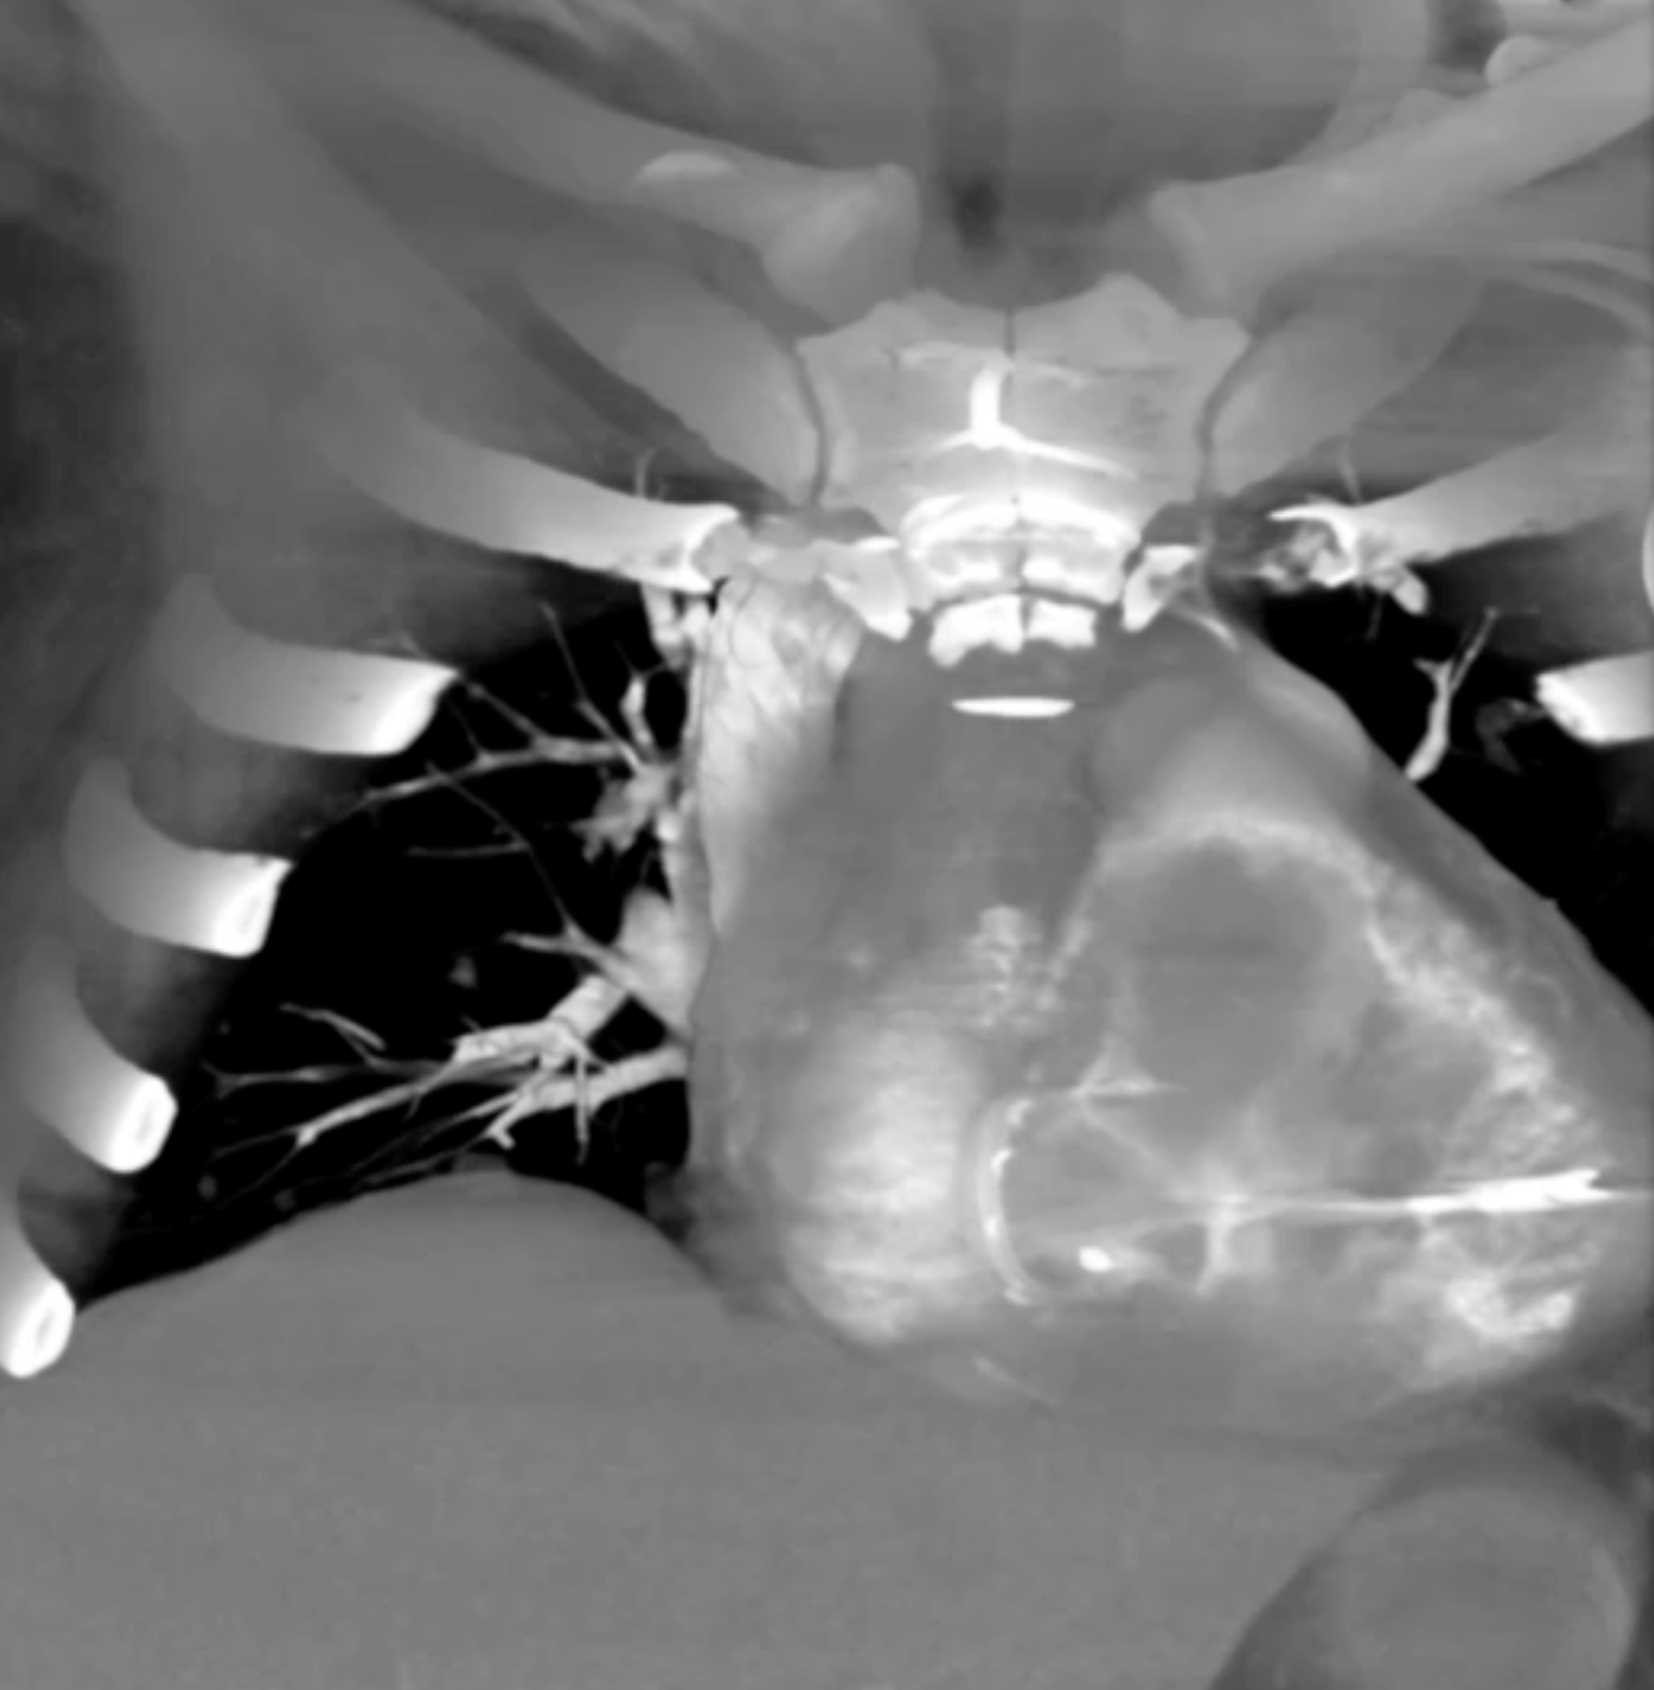

Primary Spindle Cell Carcinoma of the Right Ventricle